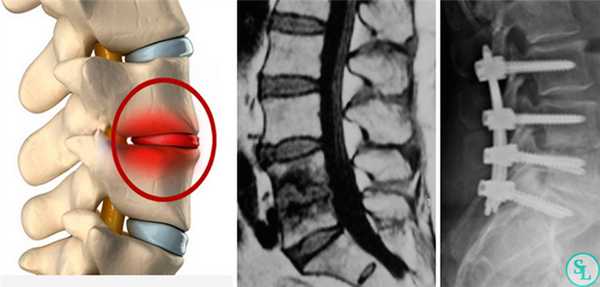

Оперативное вмешательство проводится при неэффективности консервативной терапии, выраженной нестабильности позвоночника, тяжелом неврологическом дефиците. Показаниями к операции служат признаки эпидурита, свищей, угроза сепсиса. При некупируемом болевом синдроме рассматривается возможность нейрохирургического вмешательства. Операции при спондилодисците направлены на ликвидацию очага инфекции, стабилизацию костных структур.

Целями оперативного вмешательства являются ликвидация инфекционного очага, взятие биопсии для микробиологического и гистологического исследования, декомпрессия позвоночного канала со стабилизацией и восстановлением поврежденных спинальных структур

Откачивание экссудата (дренирование) из центральной области межпозвоночного пространства – самая простая из операций при спондилодисците. Дренирование внутренних многокамерных абсцессов (внутри спинномозгового канала) занимает больше времени, т.к. требуется создавать доступ через мягкие или костные ткани.

Также проводятся ламинэктомии (удаления костных пластинок) для высвобождения корешков из-под осевших суставных отростков. Декомпрессия спинномозговых нервов – наиболее важная из причин для проведения операций.

Дискэктомия (удаление разрушенного диска) и корпэктомия (удаление фрагмента тела позвонка) позволяют полностью очистить пораженные ткани. Внедрение распорочных трансплантатов (вырезанных из костных структур, взятых в ребрах или гребне подвздошной кости) позволяет хрящевым тканям начать восстанавливаться, а фиксирующие позвоночный столб титановые конструкции временно снимут нагрузку на пострадавшие позвонки. Реабилитация занимает от 3 месяцев до полугода.

Хирургическое лечение спондилодисцита может проходить в один или два этапа. Если имеется неврологический дефицит, должна проводиться неотложная декомпрессия и стабилизация позвоночника, так как динамика развития неврологических осложнений зависит от быстроты хирургического вмешательства.

Двухэтапное вмешательство предпочтительно у пациентов без неврологического дефицита, но имеющих сопутствующую патологию. Второй этап операции проводится спустя одну или две недели после первого [5]. Вид оперативного вмешательства зависит от уровня поражения, степени деструкции и развившихся осложнений. При этом на первом этапе операции производится удаление пораженных и некротизированных тканей посредством корпоротрансверзэктомии, дискэктомии или ламинэктомии.